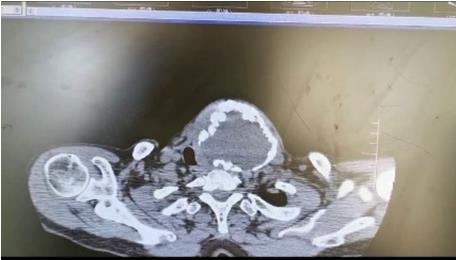

患者朱女士,68歲,頸部包塊呈進(jìn)行性增大50年,來(lái)院后彩超及CT提示左側(cè)甲狀腺腫瘤已經(jīng)超過(guò)10公分并邊緣鈣化,氣管移位較明顯,腫瘤較大屬于罕見,不僅給患者造成心理陰影,還影響了正常生活,偶有憋悶不適,進(jìn)食較大食物感哽咽不適。流動(dòng)醫(yī)院下鄉(xiāng)義診時(shí),發(fā)現(xiàn)包塊已經(jīng)很大了,影響到頸部的活動(dòng)及飲食。醫(yī)生與患者及家屬溝通講解病情,表示我們?nèi)揍t(yī)院能治療。最后患者及家屬抱著試一試的態(tài)度來(lái)到延安大學(xué)咸陽(yáng)醫(yī)院。